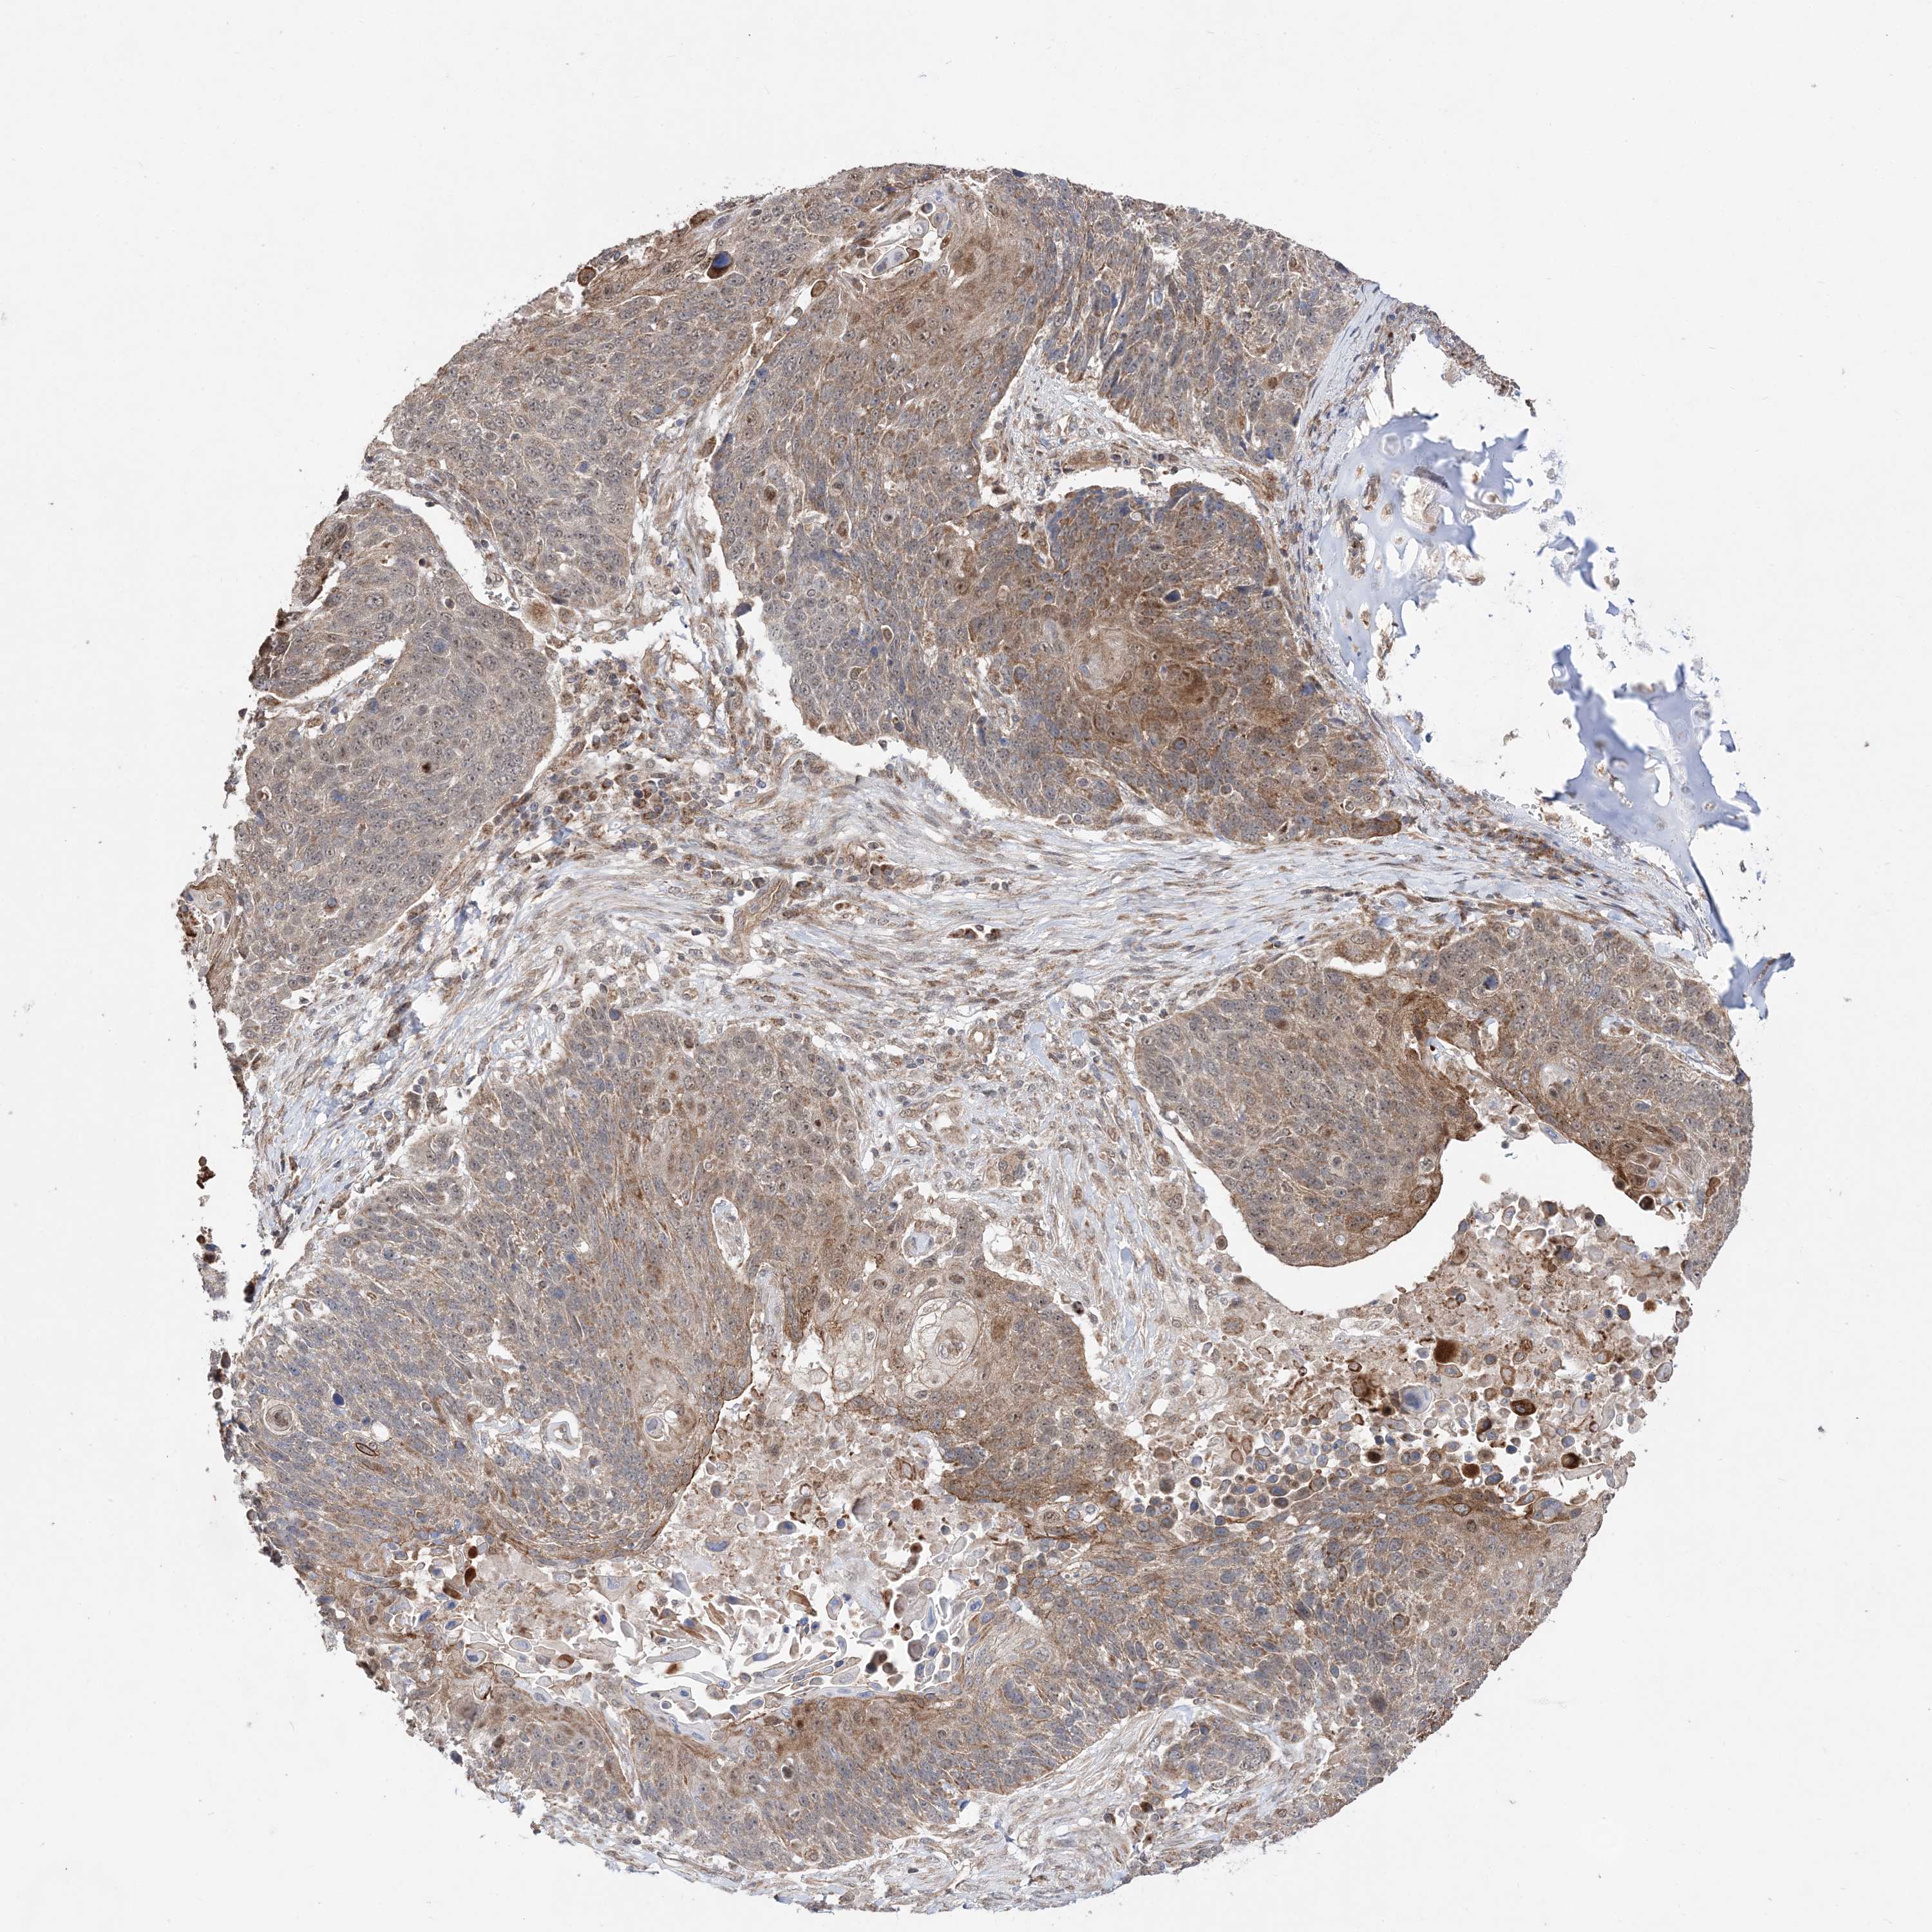

LUNG SQUAMOUS CELL CARCINOMA (TCGA) - Interactive survival scatter ploti

The Survival Scatter plot shows the clinical status (i.e. dead or alive) for all individuals in the patient cohort, based on the same data that underlies the corresponding Kaplan-Meier plots. Patients that are alive at last time for follow-up are shown in blue and patients who have died during the study are shown in red.

The x-axis shows the expression levels (FPKM) of the investigated gene in the tumor tissue at the time of diagnosis. The y-axis shows the follow-up time after diagnosis (years). Both axes are complimented with kernel density curves demonstrating the data density over the axes. The top density plot shows the expression levels (FPKM) distribution among dead (red) and alive patients (blue). The right density plot shows the data density of the survived years of dead patients with high and low expression levels respectively, stratified using the cutoff indicated by the vertical dashed line through the Survival Scatter plot. This cutoff is automatically defined based on the FPKM cutoff that minimizes the p-score. The cutoff can be changed by dragging the vertical line or by entering a cutoff value in the square labeled "Current cut-off".

Under the Survival Scatter plot the p-score landscape (black curve; left axis) is shown together with dead median separation (red curve; right axis). Dead median separation is the difference in median mRNA expression between patients who have died with high and low expression, respectively. It is calculated as follows: median FPKM expression of dead patients with high expression - median FPKM expression of dead patients with low expression. This is intended to aid the user in visually exploring custom cutoffs and the associated p-scores and dead median separation.

Individual patient data is displayed and can be filtered by clicking on one or more of the category buttons on the top of the page. Categories describing expression level and patient information include: high, low, alive, dead, female, male and tumor stages. The scale of the x-axis can be toggled between linear and log-scale by clicking on the "x log" button. Mouse-over function shows TCGA ID, patient information and mRNA expression (FPKM) for each patient.

& Survival analysisi

Kaplan-Meier plots summarize results from analysis of correlation between mRNA expression level and patient survival. Patients were divided based on level of expression into one of the two groups "low" (under cut off) or "high" (over cut off). X-axis shows time for survival (years) and y-axis shows the probability of survival, where 1.0 corresponds to 100 percent.

DALRD3 is not prognostic in Lung Squamous Cell Carcinoma (TCGA)

: 14.38

P scorei

N/A

Average pTPM 13.7

Number of samples 489